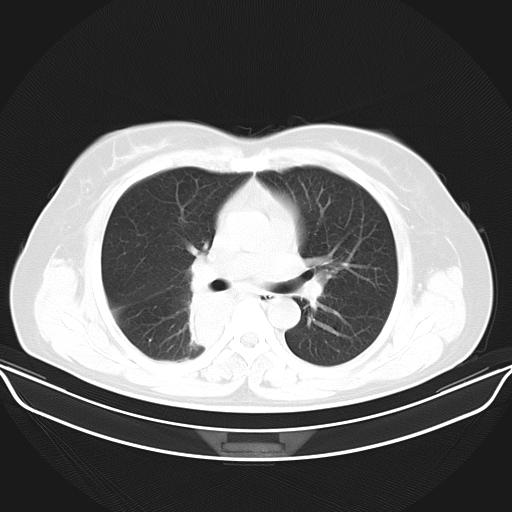

标题: CT22224:肺部肿块

f,48,主因咳嗽咳血来我院检查,无发热。

支气管镜检查未见异性细胞,抗炎治疗20天,肿块明显缩小。

支气管镜检查未见异性细胞,抗炎治疗20天,肿块明显缩小。--学习了